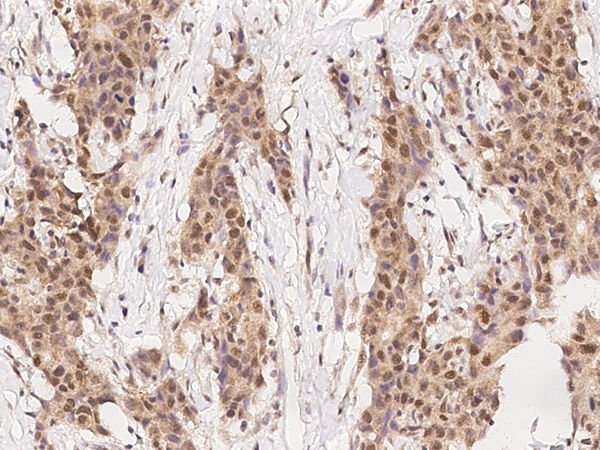

IHC (Immunohiostchemistry)

(Immunohistochemistry of paraffin-embedded Human liver cancer using ADRA1B Polyclonal Antibody at dilution of 1:25)